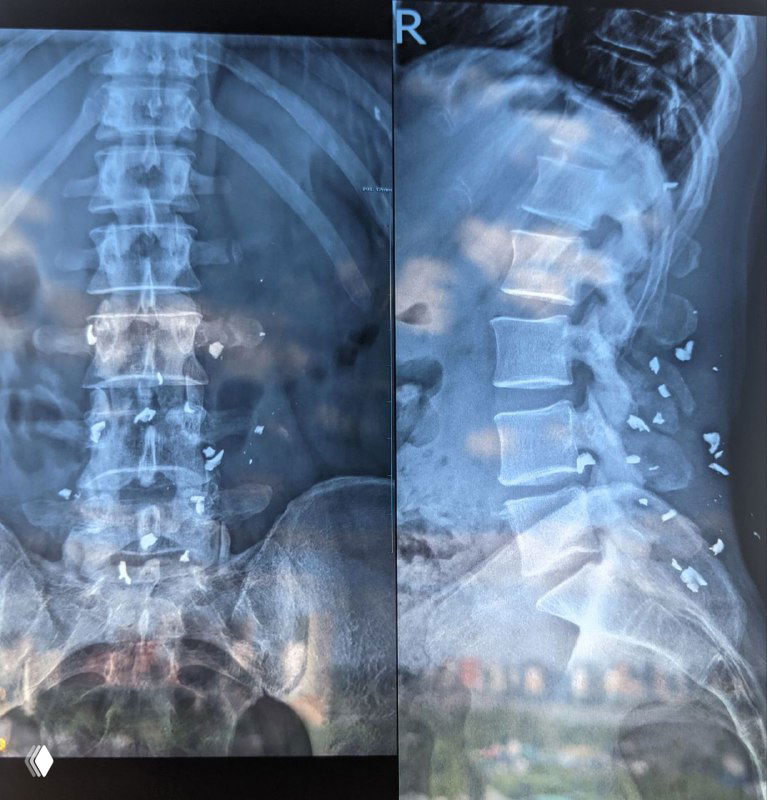

Кейс нейрохирургии: эндоскопическое удаление металлического осколка из грудного отдела позвоночника — рентген, входной разрез, извлечённые фрагменты и эндоскопия.

Краткий обзор причин удаления неугрожающих жизни осколков: хроническая боль, миграция, невозможность МРТ; автор — нейрохирург о пользе удаления.